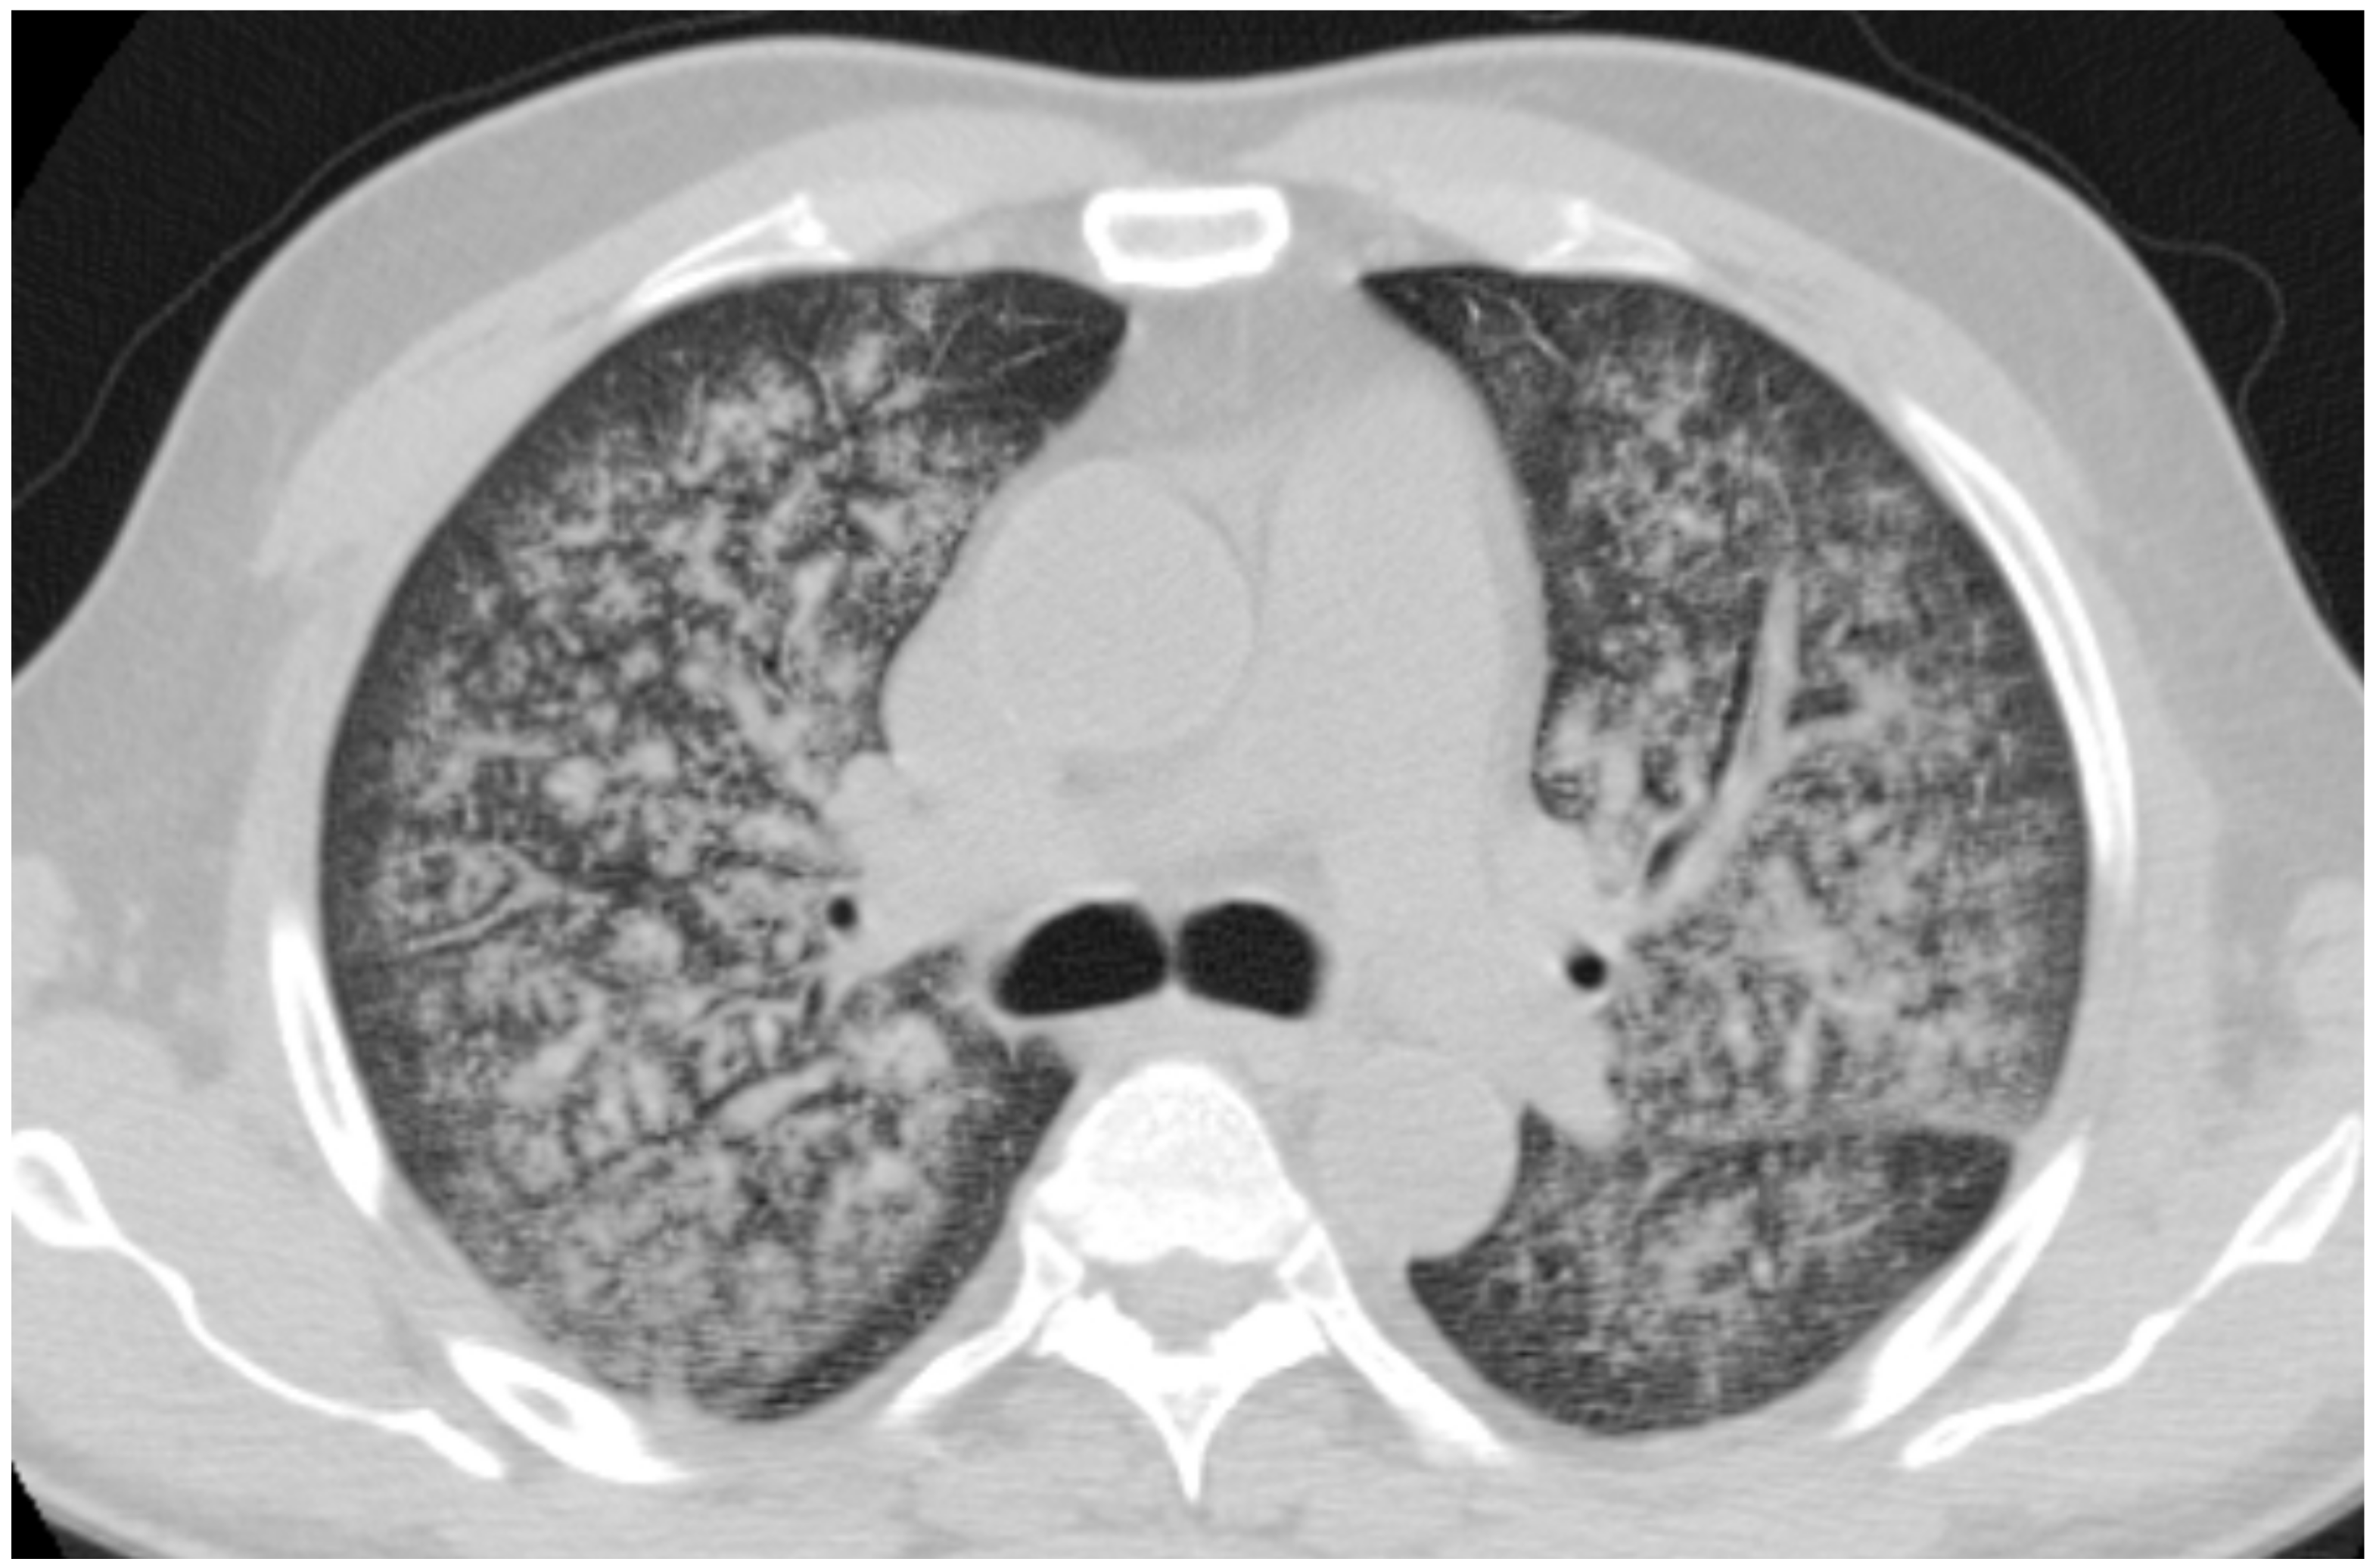

2.3. Microscopic Polyangiitis (MPA)

| MPA | GGOs due to hemorrhagic alveolitis (common); consolidation, nodules with centrilobular distribution (less common) |